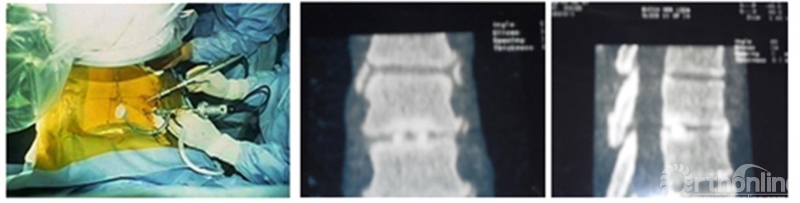

随后Osman[18]在1995年-1998年纳入患者,使用单侧双通道脊柱内镜(ipsilateral 2-portal)进行胸椎间盘切除术以及胸椎融合(取自体髂骨),并取得了令人满意的效果。但是直到2012年才得以发表一方面,为了取得美国执业医师许可,Osman不得不再次在美国接受住院医生培训,中断了研究;另一方面作者也表示担忧当时脊柱外科界对这一微创技术与理念的不热衷,作者在文中表述:“考虑当时的技术水平,我们决定等脊柱医生群体更接受这些概念后再发表(This study, as noted earlier, was carried out between 1995 and 1998, and an attempt was made to publish this work in 1999. However, in light of the state of the technology at the time, we decided to wait until the spine community was more receptive to such concepts)”。

Osman在随后的12年里一直持续定期进行单侧双通道脊柱内镜手术。除此之外,他也同时涉猎小切口显微镜技术和单通道脊柱内镜技术,但是Osman敏锐的提出:单侧双通道脊柱内镜技术中操作器械可以独立于镜头并可以使用更大的手术器械(如环钻、刮勺、磨钻、刨刀等)(The purpose of using this approach is to facilitate maneuverability of the instruments independent of the arthroscope, as well as to accommodate larger instruments, such as shavers, burs, curettes, and trephines to remove hard discs.),认为这些优点便是双通道脊柱内镜相较于单通道脊柱内镜的一种创新[18]。可以认为,DE Antoni和Osman是现代UBE/BESS技术重要的的奠基者。

图5. Osman的单侧双通道内镜手术图及自体骨融合。引自Osman SG, Schwartz JA, Marsolais EB. Arthroscopic discectomy and interbody fusion of the thoracic spine: A report of ipsilateral 2-portal approach. Int J Spine Surg 2012; 6:103-109.

18. Osman SG, Schwartz JA, Marsolais EB. Arthroscopic discectomy and interbody fusion of the thoracic spine: A report of ipsilateral 2-portal approach. Int J Spine Surg 2012; 6:103-109.